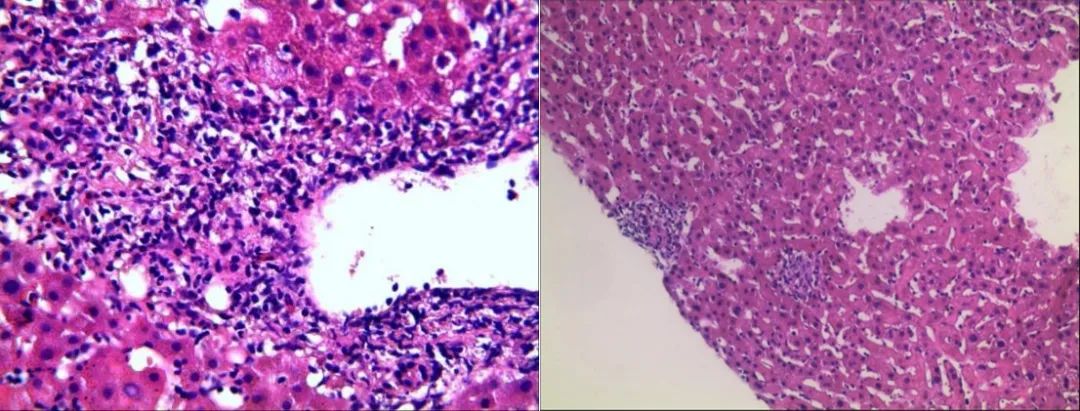

图2. 行右肝穿刺,肝组织结构大致正常,未见淤胆及脂变,肝实质散在点状坏死灶及慢性小肉芽肿结节分布;全切片查见5个较为完整的汇管区,小胆管轻度扩张,数目不增加,管周较多淋巴细胞、浆细胞及少量中性粒细胞浸润,侵蚀界面,个别汇管区组织细胞聚集、小肉芽肿形成。